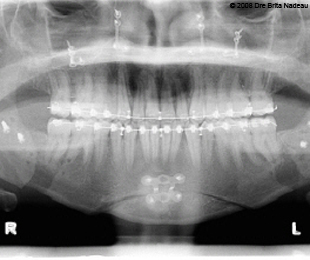

- 13 DÉCEMBRE 2007 - L'extraction de mes dents de sagesse

- Photos & radiographies